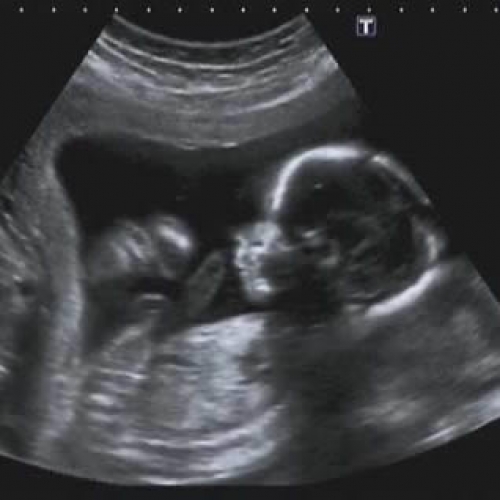

Conheça os exames realizados pela SONNAR!

A Clínica Sonnar preza pela qualidade dos seus exames, modernidade em aparelhos e ótimo atendimento.